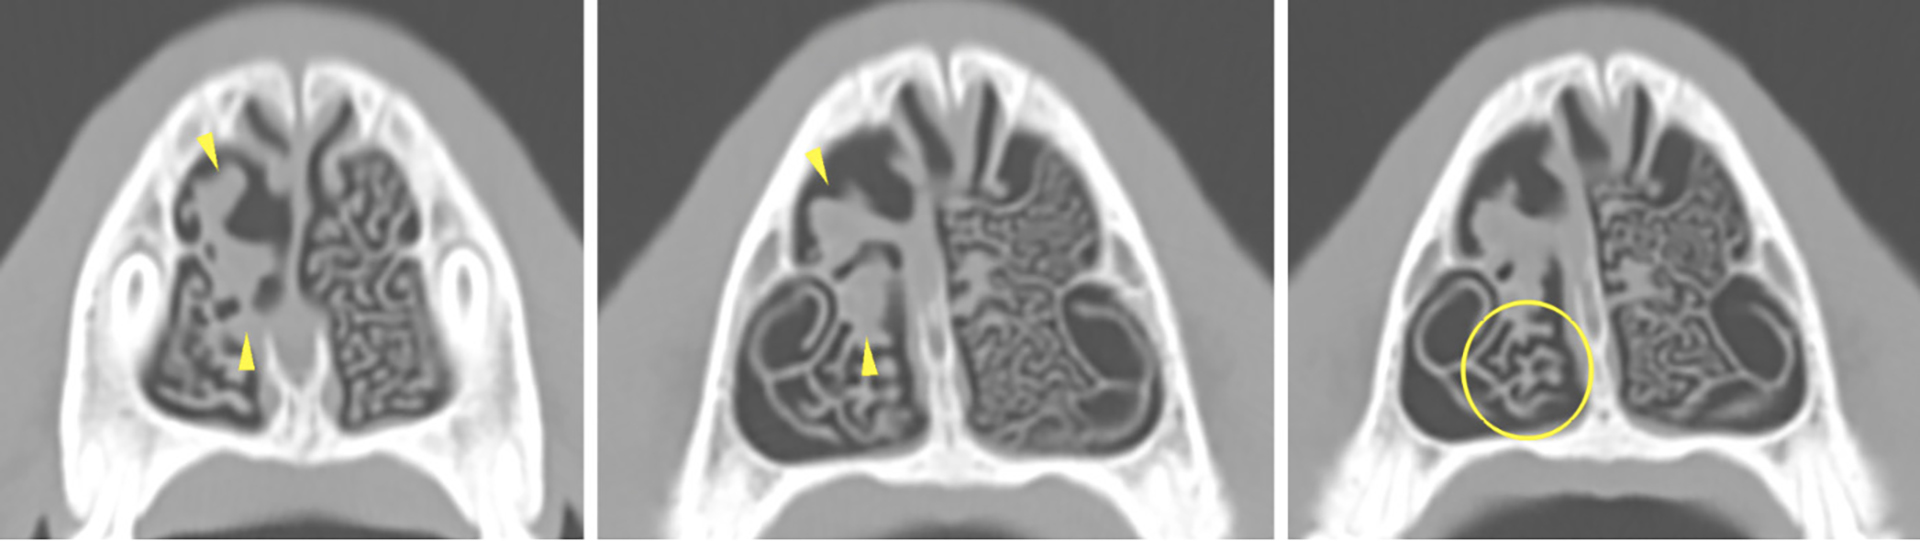

Figur 3. CT resultater. 1-2. Regional destruksjon av de dorsale og rostrale turbinatene i høyre nesehule (gule piler). Resterende turbinater er fortykkede og med unormal struktur. 3. Mer kaudalt i høyre nesehule er turbinatene redusert i antall sammenlignet med i venstre nesehule (gul sirkel).

Foto: Magnus Harjen og VET.CT

CT-rapporten beskrev funn av destruktiv rhinitt i høyre halvdel av nesehulen, og ikke-destruktiv rhinitt i venstre halvdel av nesehulen (Figur 3-5). Frontalsinusene var tilsynelatende normale. Den kribriforme platen var intakt.

Figur 4. CT resultater. 1. Dorsal multiplanar rekonstruksjon. Ødeleggelse av høyre turbinaterer og utvidelse av den nedre nesegangen (gule piler). 2-3. Redusert volum og tykkelse av høyre turbinater (3) sammenlignet med venstre turbinater (2).